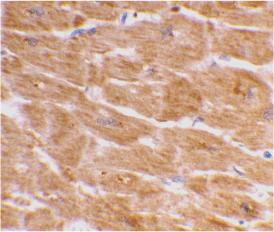

Below: Immunohistochemical staining of human heart tissue using Caspase-1 antibody at 2 µg/ml.